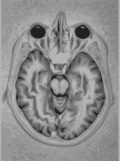

MRIPsychologists at Washington University in St. Louis have found an intriguing possibility that personality and brain aging during the golden years may be linked. Studying MRI images of 79 volunteers between the ages of 44 and 88 – who also had provided personality and demographic data – the researchers found lower volumes of gray matter in the frontal and medial temporal brain regions of volunteers who ranked high in neuroticism traits, compared with higher volumes of gray matter in those who ranked high in conscientious traits.

The orbitofrontal cortex, which is part of the prefrontal region and involved in social/emotional processing, showed similar associations with personality.

“We assumed that neuroticism would be negatively related to structural volume,” Jackson says. “We really focused on the prefrontal and medial temporal regions because they are the regions where you see the greatest age changes, and they are also seats of attention, emotion and memory. We found that more neurotic individuals had smaller volumes in certain prefrontal and medial temporal parts of the brain than those who were less neurotic, and the opposite pattern was found with conscientiousness.”